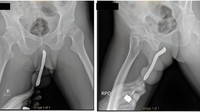

Ada juga kasus dari Indonesia. Pria yang tak disebutkan namanya dilaporkan mengalami rasa sakit yang sangat amat setelah memasukkan sikat gigi ke dalam penisnya, yang kemudian patah saat berhubungan seks. (Foto: International Journal of Surgery Case Reports).